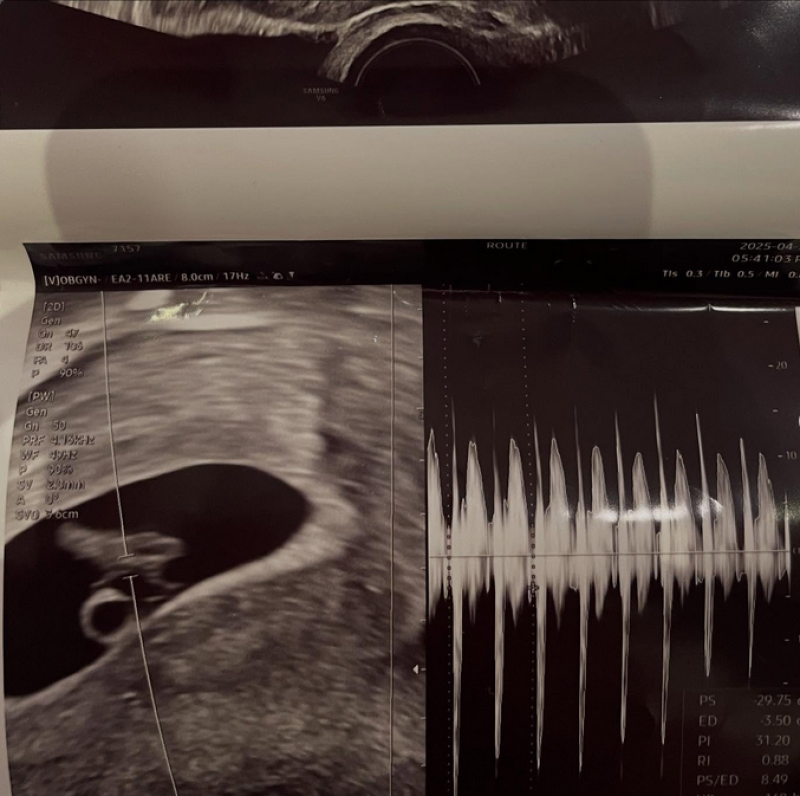

งานนี้ ซอมินแจ เปิดเผยไม่ใช่แค่เพียงผลอัลตร้าซาวด์ แต่ยังเป็นการเปิดตัวแฟนหนุ่มคนปัจจุบันอีกด้วย เธอชี้แจงว่าแม้หน้าตาของเขาจะดูเหมือนเด็ก แต่ความจริงอายุ 28 ปี และอายุน้อยกว่าเธอเพียง 4 ปีเท่านั้น ซึ่งทั้งคู่คบหาดูใจกันมาสักระยะและกำลังจะกลายเป็นพ่อแม่ในอีกไม่ช้า ท่ามกลางแฟนๆต่างแสดงความยินดีกันอย่างมาก